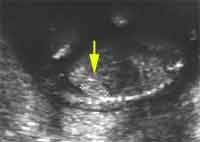

12 semaines